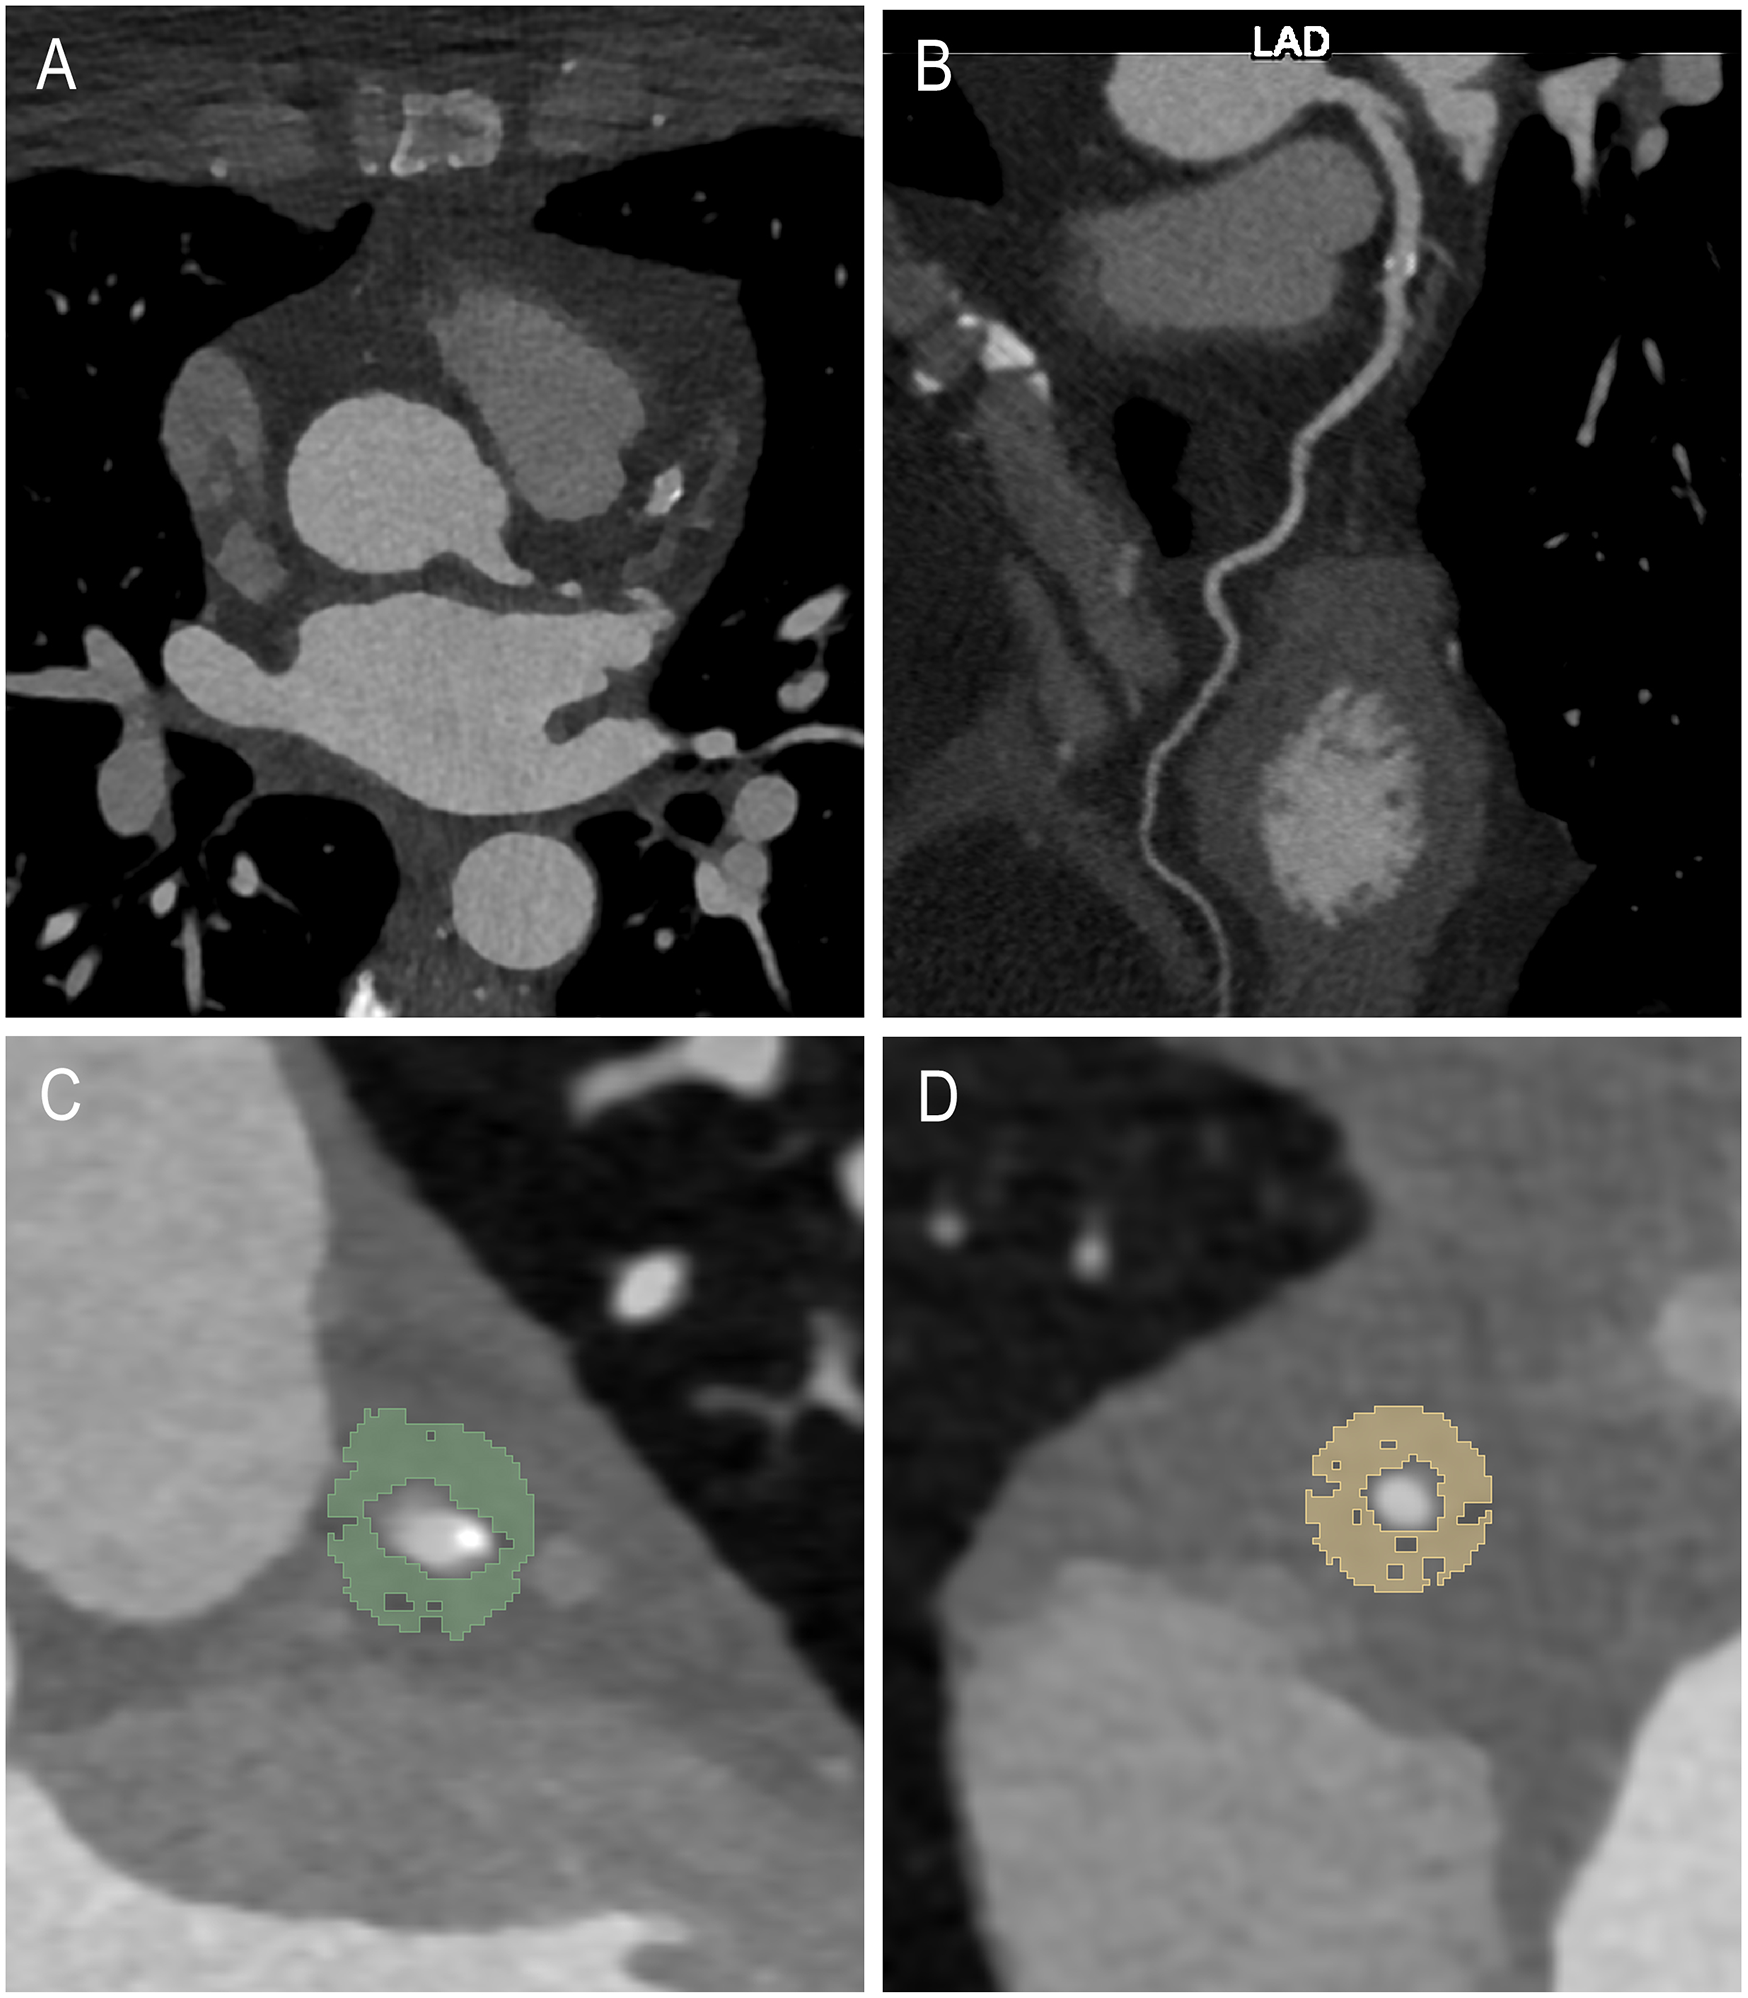

Coronary artery calcification assessment involved non-enhanced axial scans with a 3 mm slice thickness and Qr36 kernel, utilizing dedicated syngo.via software (Siemens Healthcare GmbH, Forchheim, Germany). Axial contrast-enhanced CCTA images were reconstructed using a soft vascular kernel (Bv40), with a slice thickness of 0.6 mm and an increment of 0.4 mm. After anonymization, these images were exported as Digital Imaging and Communications in Medicine (DICOM) files, subsequently converted to Neuroimaging Informatics Technology Initiative (NIFTI) format, and imported into 3D Slicer (Version 4.11), a dedicated segmentation tool (21). Coronary arteries were assessed regarding plaque morphology and degree of stenosis by a senior radiologist with a decade of cardiothoracic imaging experience and six years of segmentation expertise. Pericoronary adipose tissue segmentation of the CAD cohort and the non-CAD comparison cohort was conducted manually for the plaque-affected LAD (CAD-LAD) and the non-plaque affected RCA (CAD-RCA) in the CAD cohort and for the non-pathological LAD (non-CAD LAD) and RCA (non-CAD RCA) in the non-CAD comparison group respectively by a medical student with over one year of segmentation experience, validated by the same experienced senior radiologist. The pericoronary adipose tissue, defined as voxels between −30 and −190 Hounsfield units (HU) surrounding the RCA or LAD, was segmented along a 6 cm path beginning 1 cm past the RCA ostium and along 4 cm starting immediately distal of the bifurcation of the left main artery (LM). Segmentation was performed within a radial distance equal to the underlying vessel's diameter from the outer vessel wall. Figure 1 offers an axial view illustrating an example of pericoronary adipose tissue segmentation.

Figure 1

Example case of a 53-year-old female with a plaque in the LAD including the axial view (A), a multiplanar reconstruction of the LAD (B) and example segmentations of the LAD (C) and RCA (D).